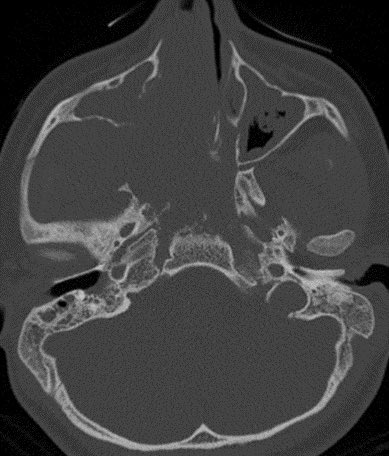

⭐️ Classic case: what’s the most likely diagnosis in this 12 y/o M presenting with stuffy nose and epistaxis? #ENT #Peds #medicine #radres #futureradres #Neurology #neurosurgery @ASHNRSociety @Radiopaedia

⭐️ Classic case: what’s the most likely diagnosis in this 12 y/o M presenting with stuffy nose and epistaxis? #ENT #Peds #medicine #radres #futureradres #Neurology #neurosurgery @ASHNRSociety @Radiopaedia